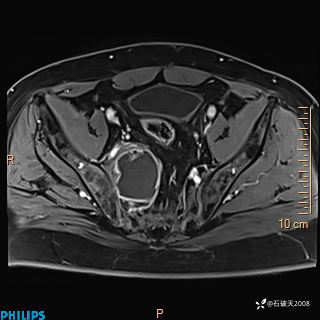

现病史:7个月前患者因骶尾部占位就诊于北京大学人民医院,MRI示:骶骨右侧及右骶前占位,考虑骨巨细胞瘤可能,动脉瘤样骨囊肿可能,神经源性肿瘤待排。行手术治疗,术后病理回示:XXXXX。术后给予对症治疗,具体不详,恢复良好。近几个月反复出现发热,伴骶尾部不适,多次住院给予对症治疗,2天前患者无明显诱因再次发热伴骶尾部不适,无大小便失禁,为求进一步治疗,遂门诊来我院,在门诊初步检查后,以“骶尾部肿物”为诊断收入我科。入院来患者神志清,精神一般,饮食睡眠可,大小便无明显异常,体重无下降。

2023年3月份MRI影像

增强轴位